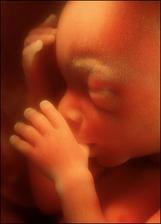

Druhé tři měsíce těhotenství jsou pro spoustu žen nejkrásnějším a nejpříjemnějším obdobím za celou dobu těhotenství.

- II. trimestr = 13. - 28. týden těhotenství